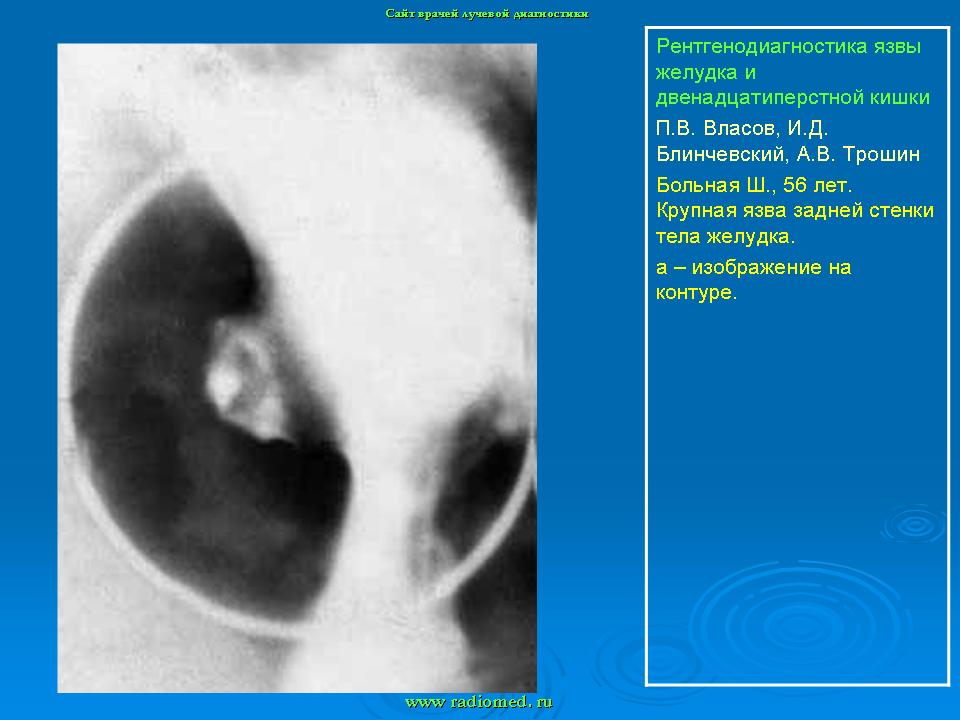

Пищеварительная система. Рентгенодиагностика язвы желудка и 12-ти перстной кишки. +

Рентгенодиагностика язвы желудка и 12-ти перстной кишки.